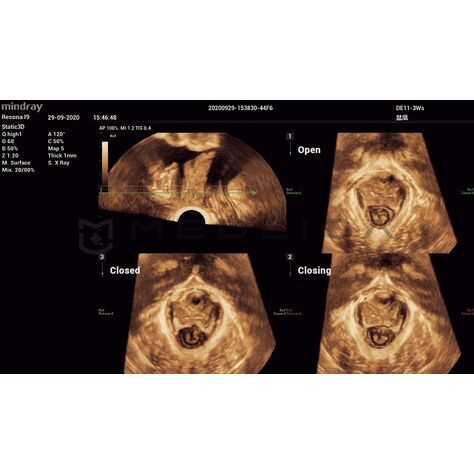

Программное обеспечение для автоматических измерений параметров и оценки функции мышц тазового дна.

Smart Pelvic - новое решение, позволяющее значительно упростить диагностическую процедуру и свести к минимуму время исследования функций мышц тазового дна. Благодаря чрезвычайно простому пользовательскому интерфейсу, программа генерирует стандартную систему координат и автоматически просчитывает все связанные измерения в течение нескольких секунд.